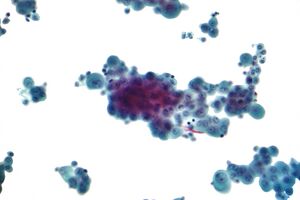

Diagnosis of mesothelioma can be suspected with imaging but is confirmed with biopsy. It must be clinically and histologically differentiated from other pleural and pulmonary malignancies, including reactive pleural disease, primary lung carcinoma, pleural metastases of other cancers, and other primary pleural cancers.[12]

Imaging

Diagnosing mesothelioma is often difficult because the symptoms are similar to those of a number of other conditions. Diagnosis begins with a review of the patient's medical history. A history of exposure to asbestos may increase clinical suspicion for mesothelioma. A physical examination is performed, followed by chest X-ray and often lung function tests. The X-ray may reveal pleural thickening commonly seen after asbestos exposure and increases suspicion of mesothelioma.[15] A CT (or CAT) scan or an MRI is usually performed. If a large amount of fluid is present, abnormal cells may be detected by cytopathology if this fluid is aspirated with a syringe.[11] For pleural fluid, this is done by thoracentesis or tube thoracostomy (chest tube); for ascites, with paracentesis or ascitic drain; and for pericardial effusion with pericardiocentesis. While absence of malignant cells on cytology does not completely exclude mesothelioma, it makes it much more unlikely, especially if an alternative diagnosis can be made (e.g., tuberculosis, heart failure).[citation needed] However, with primary pericardial mesothelioma, pericardial fluid may not contain malignant cells and a tissue biopsy is more useful in diagnosis.[11] Using conventional cytology diagnosis of malignant mesothelioma is difficult, but immunohistochemistry has greatly enhanced the accuracy of cytology.[citation needed]

Biopsy

Generally, a biopsy is needed to confirm a diagnosis of malignant mesothelioma. A doctor removes a sample of tissue for examination under a microscope by a pathologist. A biopsy may be done in different ways, depending on where the abnormal area is located. If the cancer is in the chest, the doctor may perform a thoracoscopy. In this procedure, the doctor makes a small cut through the chest wall and puts a thin, lighted tube called a thoracoscope into the chest between two ribs. Thoracoscopy allows the doctor to look inside the chest and obtain tissue samples. Alternatively, the cardiothoracic surgeon might directly open the chest (thoracotomy). If the cancer is in the abdomen, the doctor may perform a laparoscopy. To obtain tissue for examination, the doctor makes a small incision in the abdomen and inserts a special instrument into the abdominal cavity. If these procedures do not yield enough tissue, an open surgical procedure may be necessary.[citation needed]

Immunochemistry

Immunohistochemical studies play an important role for the pathologist in differentiating malignant mesothelioma from neoplastic mimics, such as breast or lung cancer that has metastasized to the pleura. There are numerous tests and panels available, but no single test is perfect for distinguishing mesothelioma from carcinoma or even benign versus malignant. The positive markers indicate that mesothelioma is present; if other markers are positive it may indicate another type of cancer, such as breast or lung adenocarcinoma. Calretinin is a particularly important marker in distinguishing mesothelioma from metastatic breast or lung cancer.[12]